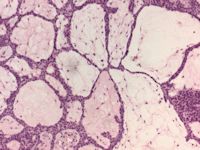

![Fibroepithelioma (Pinkus tumor) (click on photo to enlarge) [source: www.huidziekten.nl] Fibroepithelioma (Pinkus tumor)](../../../images/pinkus-tumor-3z.jpg) |

fibroepithelioma

(Pinkus) |

PA:

De histologie toont dunne anastomoserende strengen basaloide keratinocyten (soms

squameuze differentiatie) die ruimten gevuld met stroma omlijsten als 'kozijnen

rond een ruit'. Driedimensionaal gaat het om een honingraat vormige of sponsachtig

opgebouwde tumor die begint in de papillaire dermis en die bij groei de papillaire

dermis opblaast en een gesteelde laesie vormt. In de ruimten groeien soms structuren

die lijken op haarzakjes in vroege embryonale ontwikkeling, die 'follicular

germ-like structures' worden genoemd. Immunokleuringen tonen vaak (85%) cytokeratin

20 (CK20, Merkel cellen) en BCL-2 (proto-oncogen), soms androgeen receptoren,

soms zwakke aankleuring p53 of proliferatie marker Ki-67. Sommige pathologen

beschouwen het als een gefenestreerde variant van een trichoblastoom. Het niet-aggresieve

gedrag past daar goed bij. Cysteuze varianten komen voor.